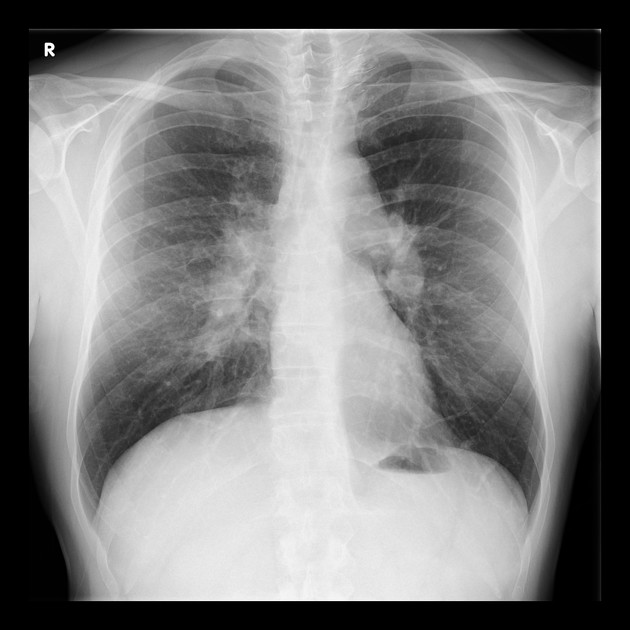

Pulmonary metastases

Metastatic deposits in the lung

Metastases to the lung Multiple nodules of varying size, well-defined margins, random distribution; may cavitate depending on primary.